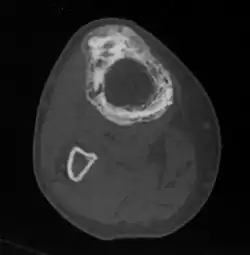

Die übermäßige Ausscheidung von Calcium kann zu Nierensteinen führen, die vermehrte Knochendurchblutung begünstigt eine Herzinsuffizienz. Durch die übermäßige Teilungsaktivität der Knochenzellen kommt es in etwa 1 % der Fälle zur Entwicklung eines bösartigen Knochentumors. Wenn derartige Komplikationen vermutet werden, ist eine Computertomografie oder Kernspintomografie sinnvoll.

Wesentlich für die Diagnose ist das Röntgenbild, in dem schon im Frühstadium der Erkrankung die Osteolyse nachgewiesen werden kann. Der erhöhte Knochenumbau kann mittels Knochenszintigraphie nachgewiesen werden.